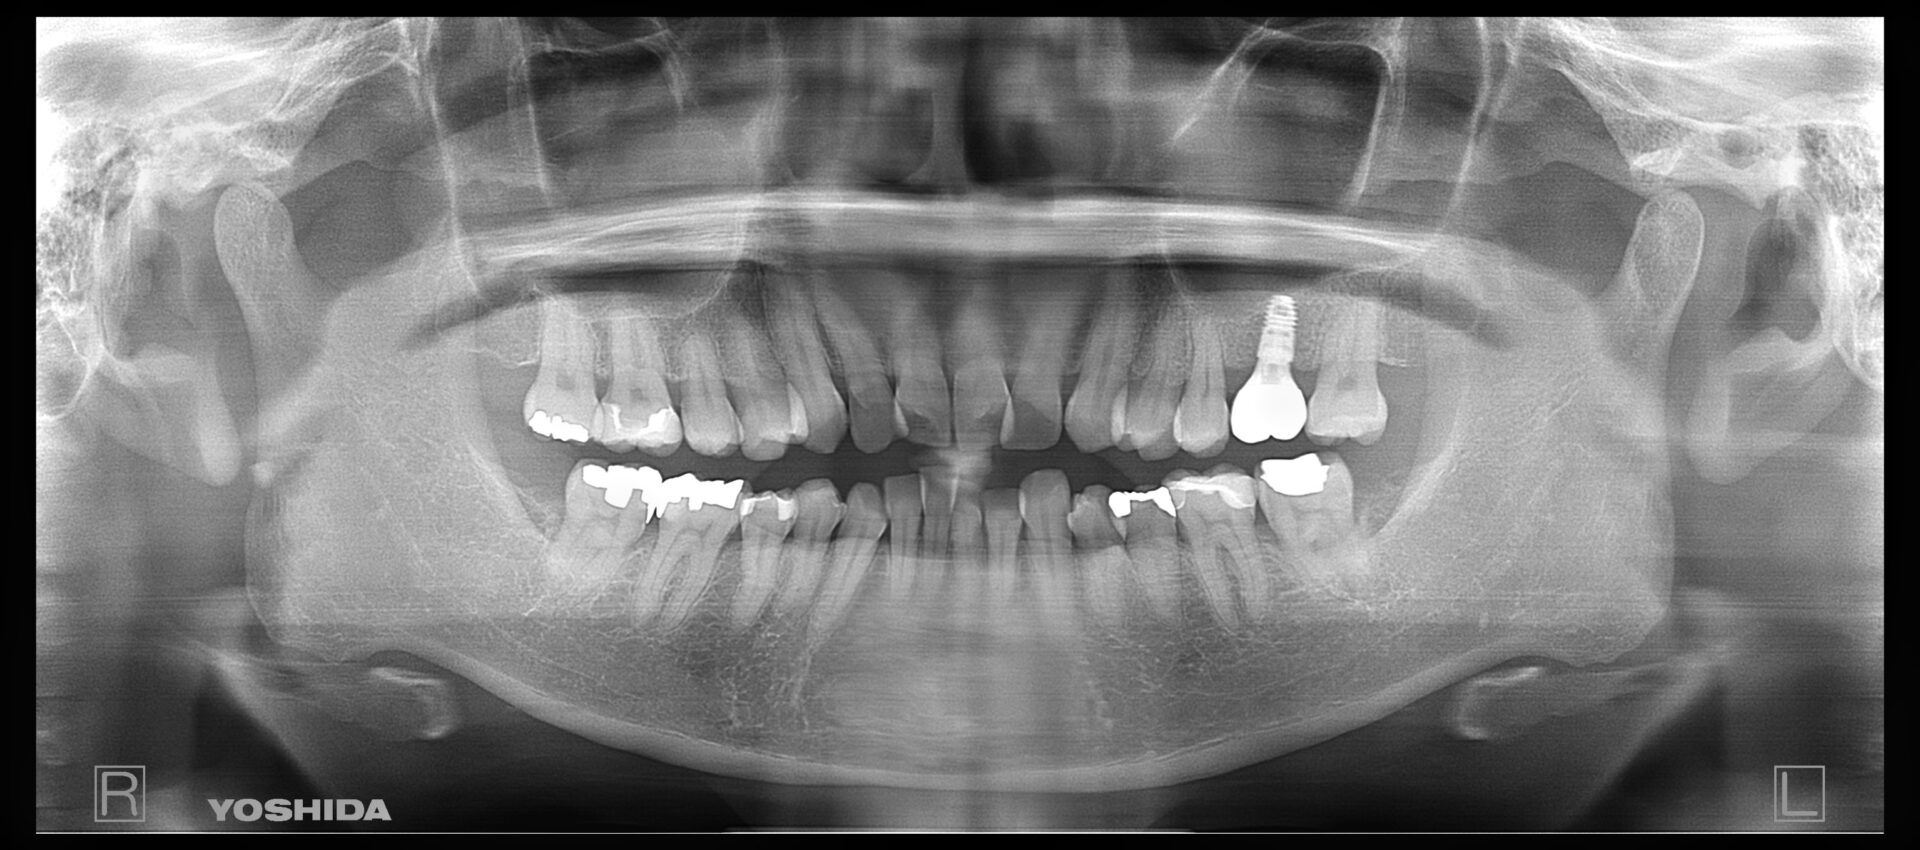

40代男性

R5.4

左下7のインプラント埋入を検討

画像

R7.5

4ヶ月前に埋入したインプラントの経過観察

R7.12

11ヶ月慎重に様子を見て上部の被せ物を被せることができました

左下7番部にエナメル上皮腫(良性腫瘍)が認められた患者様が、将来的にインプラント治療をご希望されました。

まずは安全を最優先に、口腔外科にて腫瘍の摘出手術を行っていただきました。

手術後は、インプラントを支えるための骨がどの程度回復するか慎重に経過を観察し、約2年間、骨の再生を待ちながらフォローアップを続けました。しかし、残念ながら想定したほど骨量が回復せず、理想的な位置(もう少し奥の部位)にインプラントを埋入することが難しい状態でした。

そこで、工学的・解剖学的条件を総合的に検討し、歯科技工士とも綿密に相談した上で、安全性と長期安定性を優先し、手前側の位置にインプラントを埋入するという治療計画に変更しました。

結果としてインプラントは良好に骨と結合し、現在は問題なくお食事もできており、とても満足して生活されているとのことです。

難症例ではありましたが、口腔外科との連携、慎重な経過観察、そして適切な位置へのインプラント埋入により、安全かつ確実な治療結果を得ることができました。